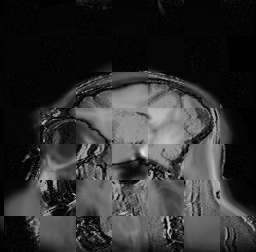

For each of the 10 subjects, we show checkerboard slices in each direction (1) before registration, first row; (2) after rigid->scaleversor->affine registration, second row; and (3) after BSpline registration, third row.

Hugo